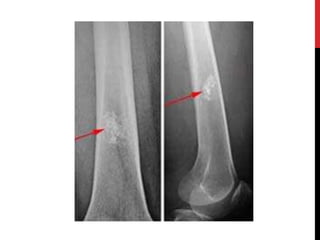

OSTEOID OSTEOMA

Benign bone forming tumor small but very painful

It has a center of growing cells, called a nidus =vascularized tumer(less

than 1 cm) surrounded by a hard shell of reactive thickened bone.

Clinical Features.

• Age: young persons 20-30y

• Sex: males:female - 3:1.

• Site: Frequently in the femur or in the tibia.

• In head and neck→ Cervical spine > mandible and maxilla.

• Chief symptoms → severe pain → unrelenting and sharp, worse at night.

• Classically, the pain is relieved by aspirin.

Treatment:

• is surgically cutting out of the entire

tumor, particularly the central core, for a

good outcome